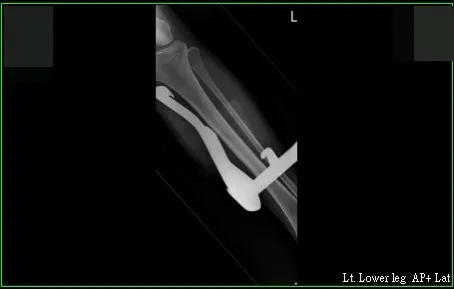

在X光片影像中,可看到長達23公分的中柱,直直插在李小姐左腿裡。讀者提供